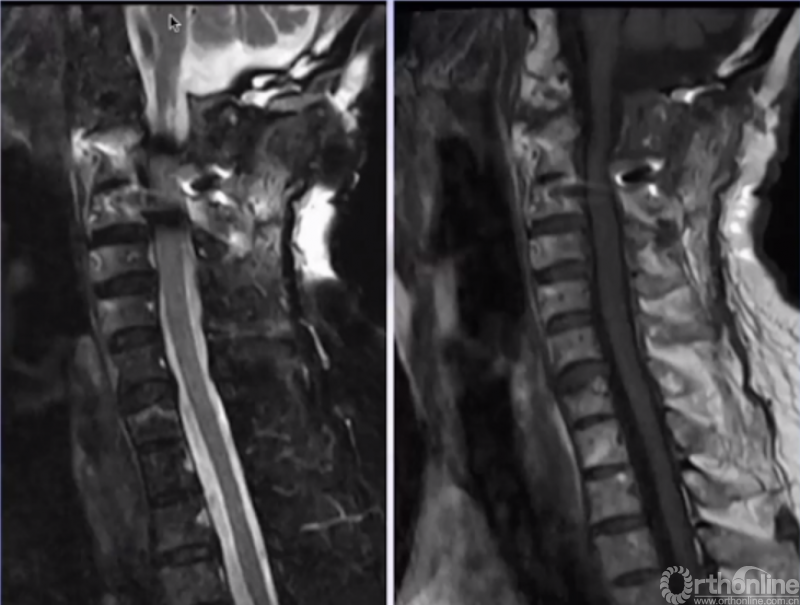

MRI

术后MRI(患者术后四肢麻木、乏力,发音、吞咽困难改善。)